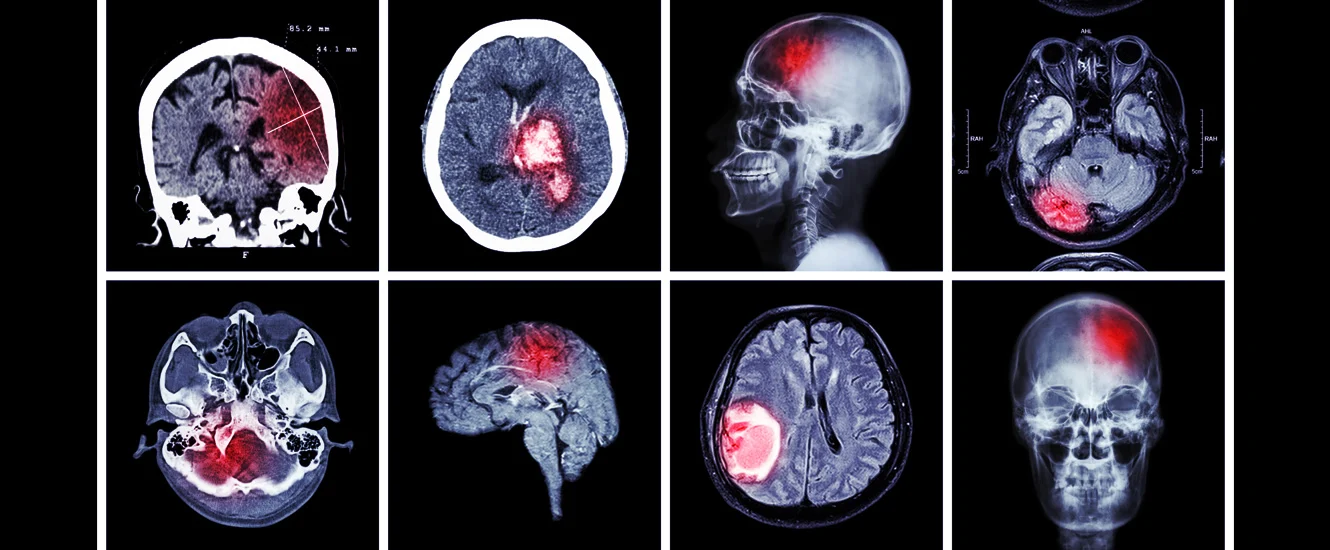

Stroke Prevention and Treatment

A Steady Decline in Stroke Deaths

Despite the continued and steady decline of deaths due to strokes, they continue account for 1 of every 20 deaths in the US. The decline of deaths due to strokes can be attributed to early identification of strokes, primary prevention, and secondary prevention.